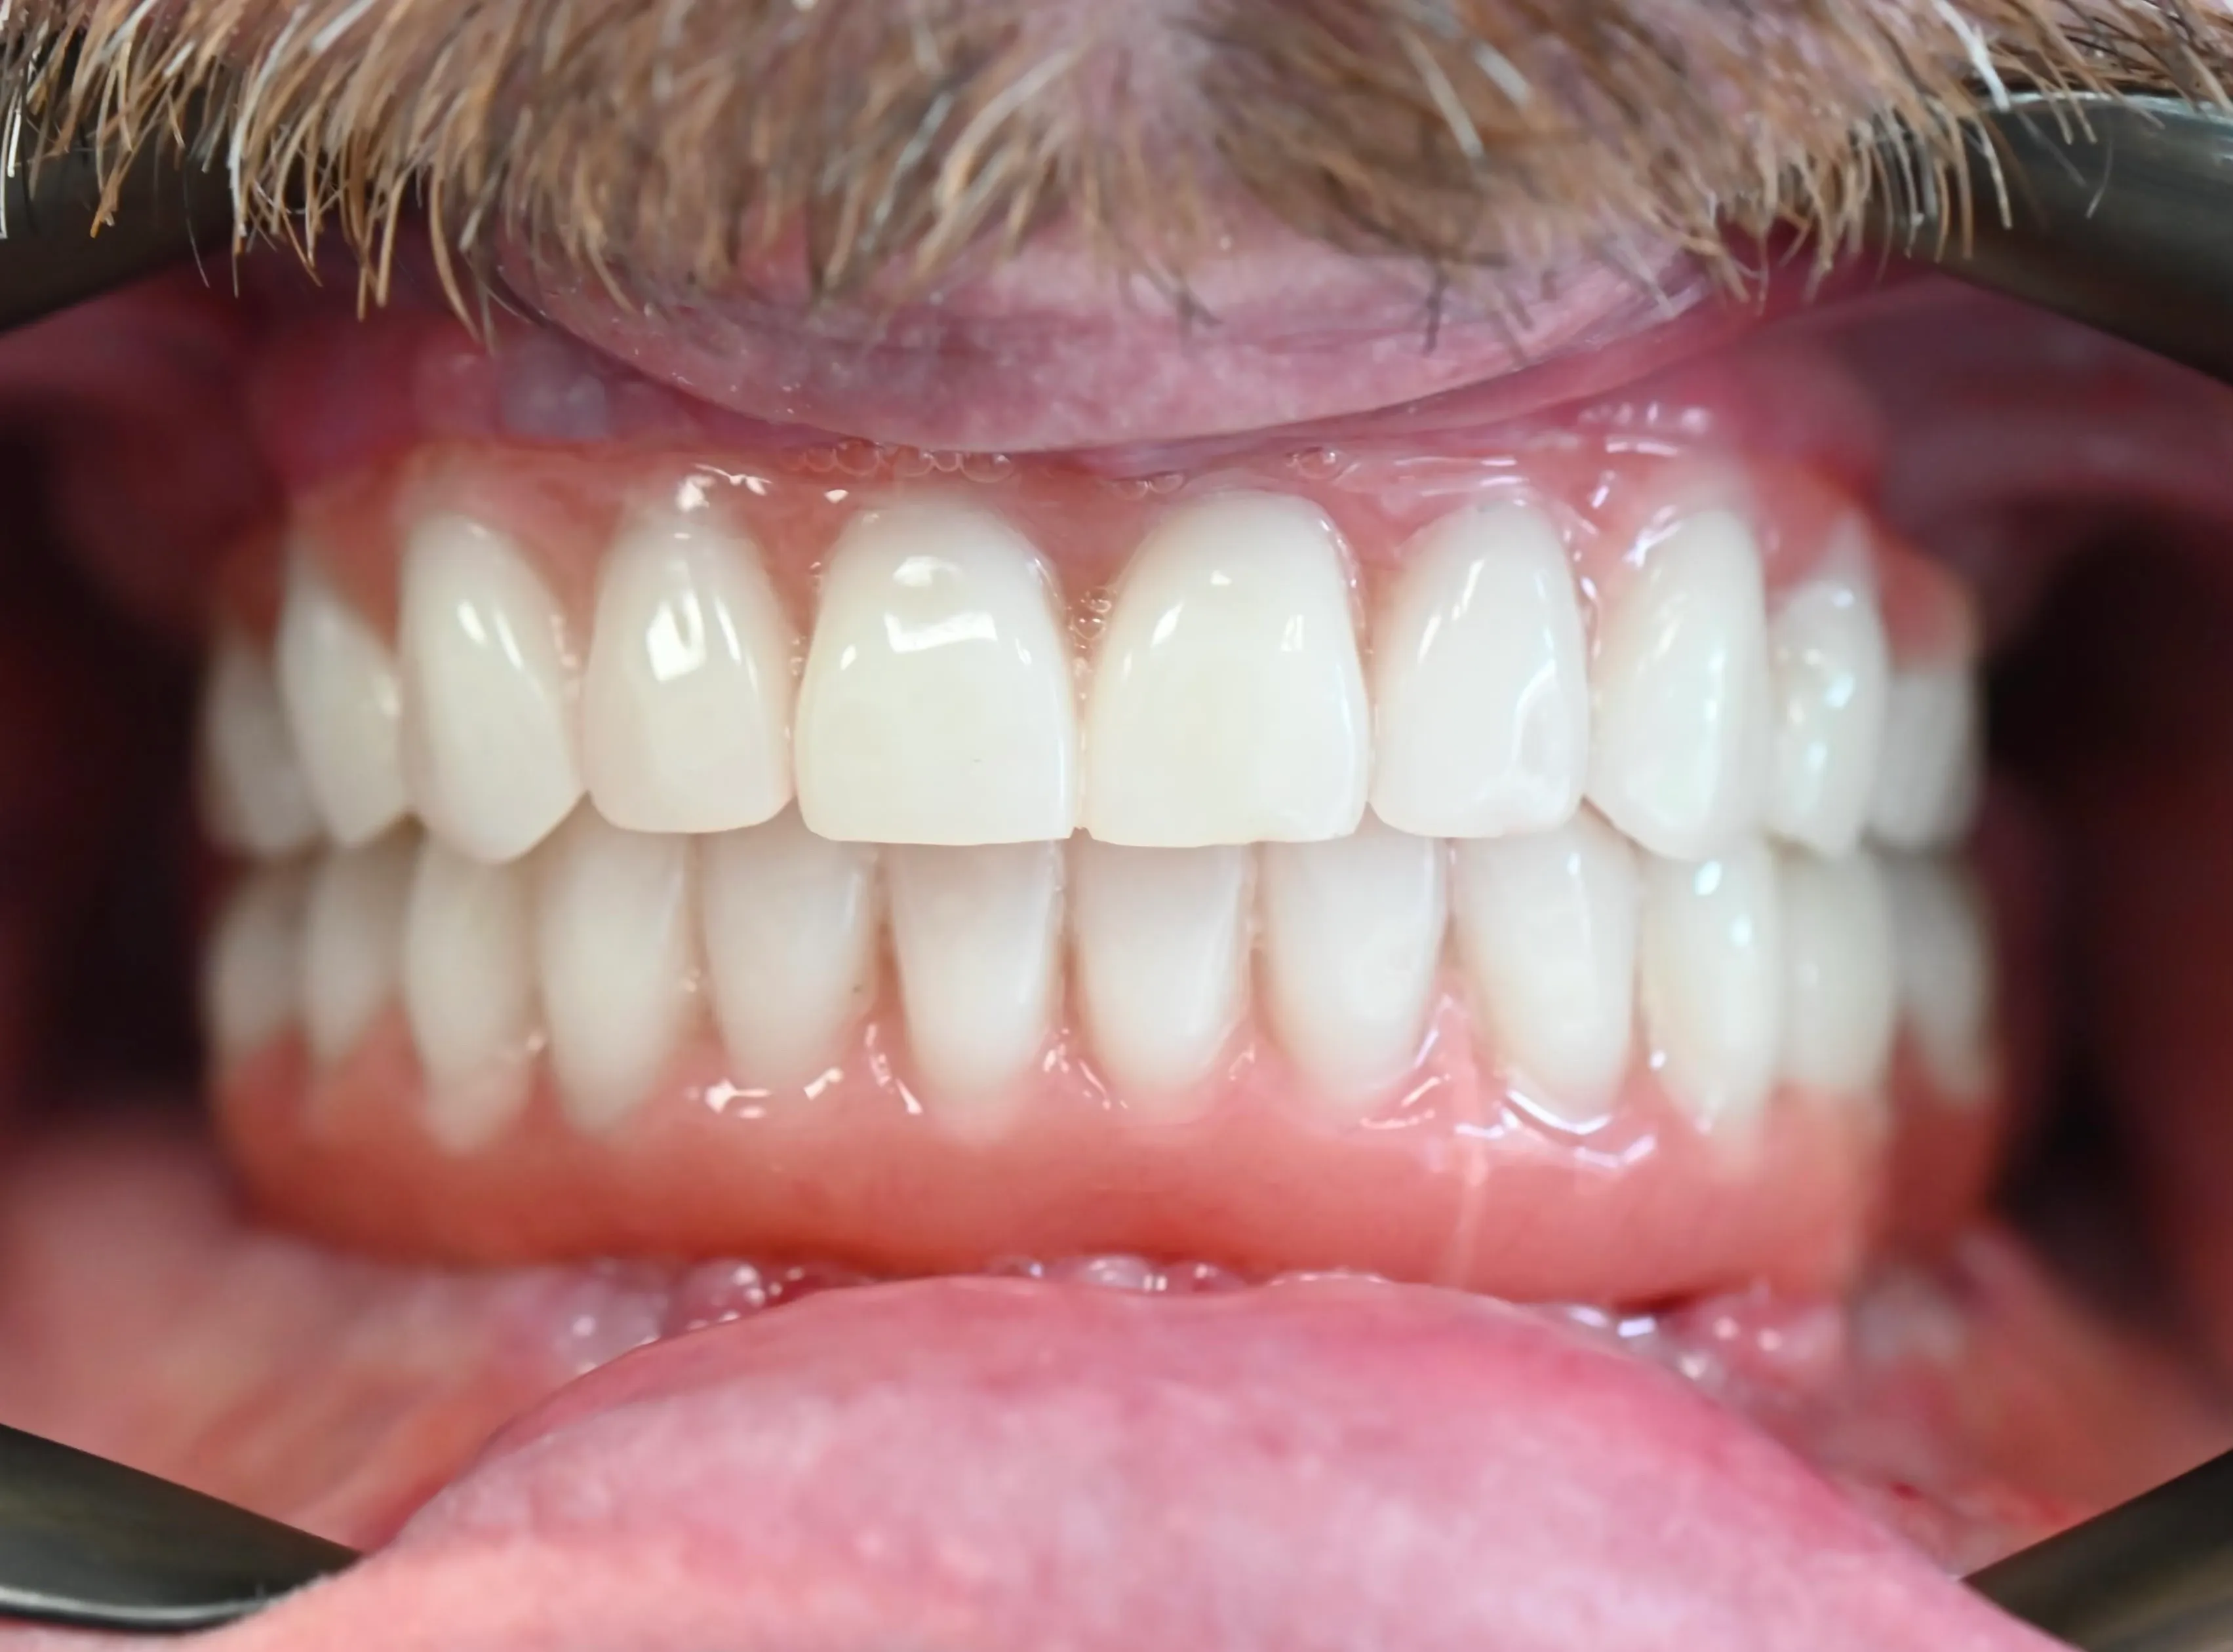

Full-Arch Implant Rehabilitation

All-on-4 surgical guide for complete upper arch restoration